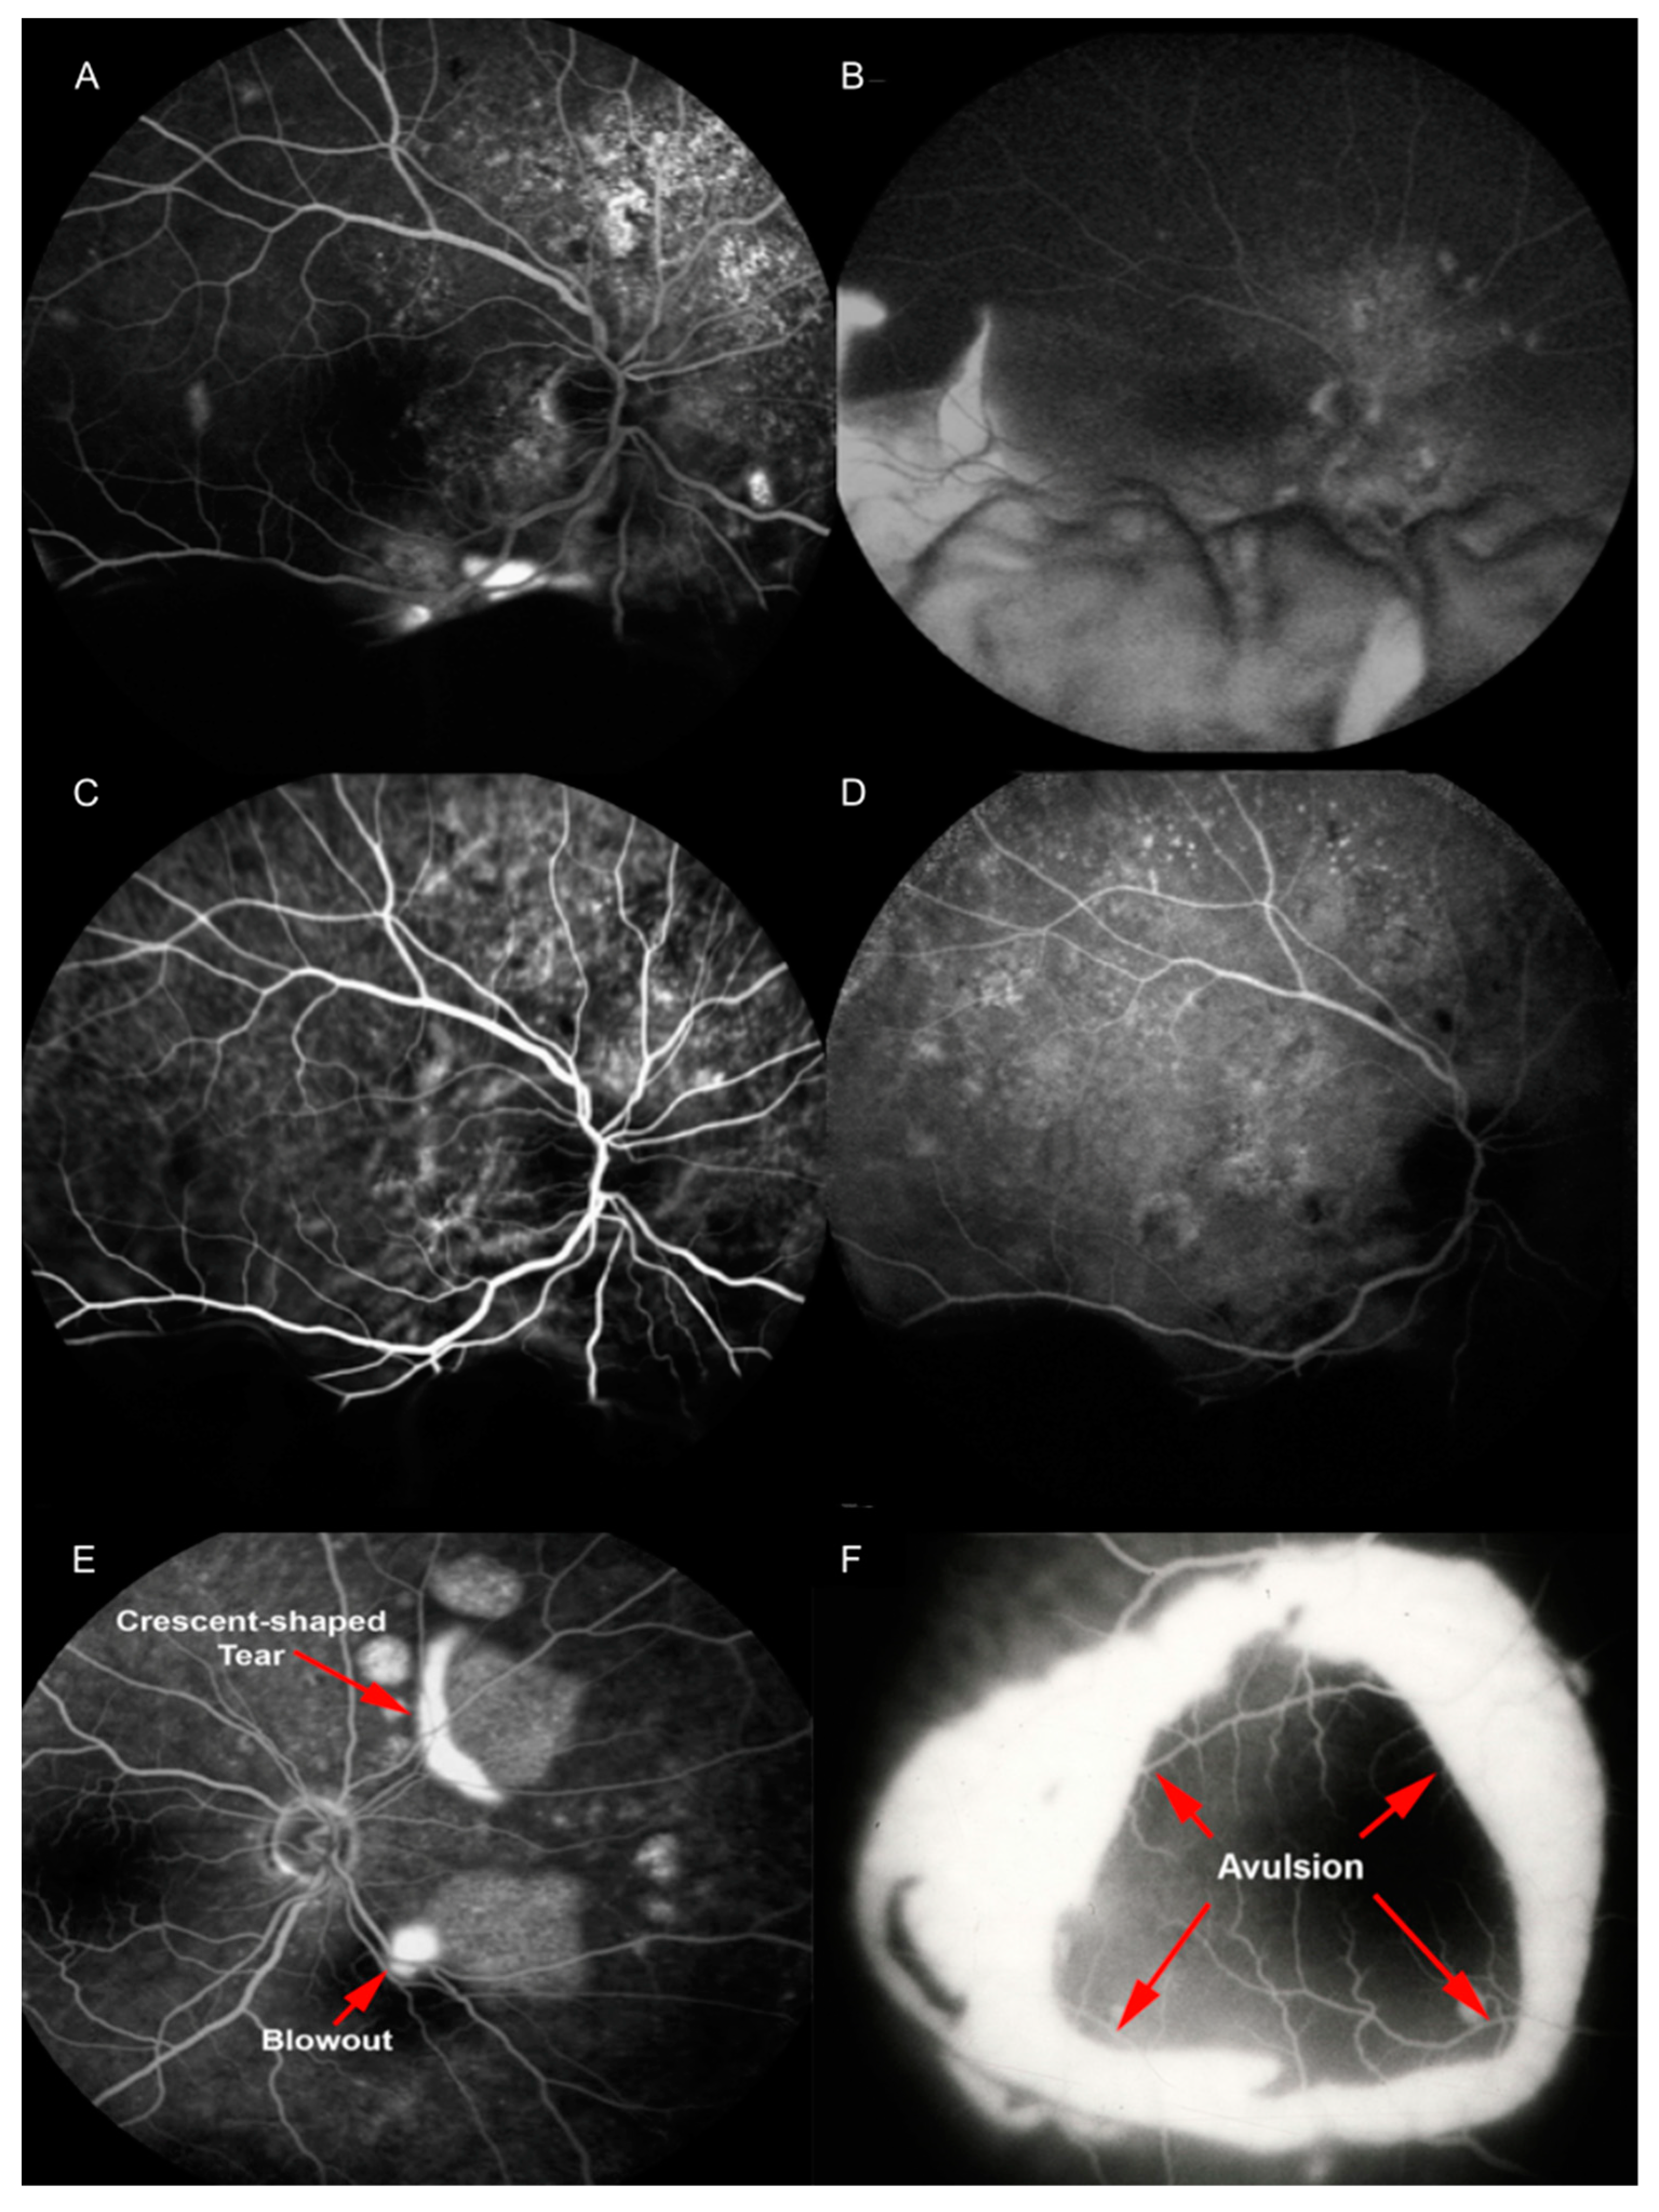

In the phases preceding bCSCR development, fluorescein angiography (FA) reveals focal areas of hyperfluorescence (blowouts) within PEDs [6].

When bCSCR develops, FA highlights multiple RPEs tears as early hyperfluorescence and late staining (2–22, mean 6.7), at sites correlating to the position of previous PEDs [6]. The retina is attached to the area devoid of RPE by subretinal fibrin at sites of RPE tears [6]. A pooling of the sub-neurosensory retinal space is also highlighted [3]. This hyperfluorescence descends inferiorly conforming to the dependent retinal detachment [4]. Furthermore, slow and rather diffuse bilateral leakage attest diffuse decompensation of the RPE [22]. In particular, the crescent RPE tear appears as a window defect (the bare choroid) next to an hypofluorescence (the rolled RPE layer), in all angiographic phases if it has a crescent shape type [20]. Conversely, concentric RPE tear appears as an island of retracted RPE tissue at the center of the tear, with a hyperfluorescent area all around [6].

In the case of peripheral retinal ischemia and neovascularization, wide-field FA can detect retinal capillaries obliteration and neovascularization with profuse leakages at the junction between perfused and non-perfused retina during the late angiographic phase [18,22]. Finally, no disk leak or vasculitis are detected [14].

Indocyanine green angiography (ICGA) shows dilated choroidal vessels with choroidal hyperpermeability, and in 20% of cases, a filling delay of choroidal circulation [23,24]. In late phases, PED demonstrates persistent hypofluorescence [13] (Figure 4).

Figure 4. Fluorescein angiography (FA) reveals multiple areas of leakage at the posterior pole in the early phase (A); with consequent pooling of the subretinal space and the dependent exudative retinal detachment (B). Indocyanine green angiography (ICGA) shows hyperpermeable and dilated choroidal vessels (C); in late phase pigment epithelial detachment (PED) it appears still hypofluorescent (D). FA shows focal area of hyperfluorescence (blowouts) within PED and an RPE tear with crescent shape (E). FA delineates a concentric RPE tear, with a retracted RPE at the center (F). Reproduced and merged with permission from [6,14].